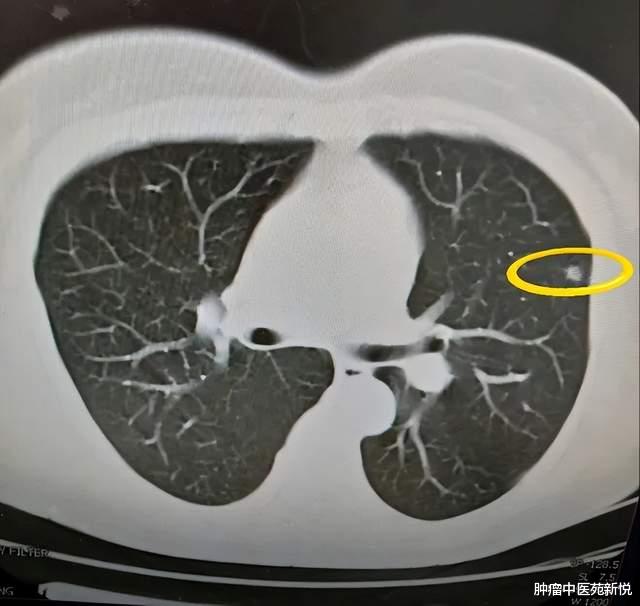

随着体检的普及 , 不少人在体检时 , 会发现自己肺部居然有结节出现 。 除了长期抽烟的人外 , 很多不抽烟的人女性 , 在体检报告中也很常见 。

尤其是一听到结节 , 不少人都联想到肺癌了 , 整天担惊受怕的 , 但其实肺结节不等于肺癌 , 大可不必过于紧张 。 查出肺结节 , 很多人都在饮食上有所禁忌 , 认为不能喝冰咖啡 。